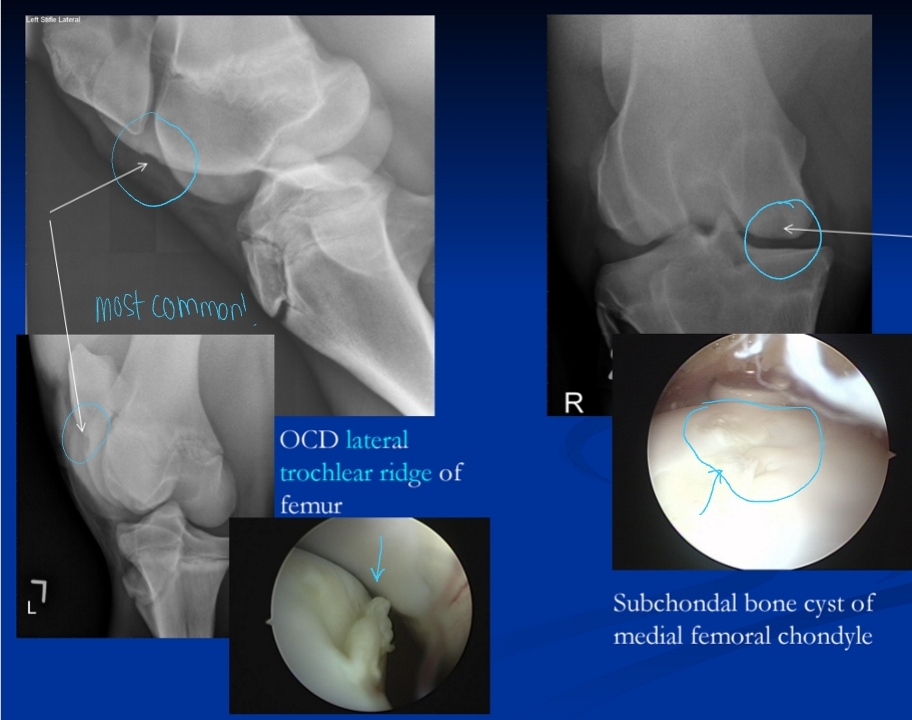

Subchondral Cystic Lesions and Osteochondrosis Dissecans (OCD)

Et: Osteochondrosis lesion

genetics, rapid growth, Ca:P imbalances

Sig: Young, TB, QH, male

Common

Cs: Effusion, lameness

Stifle > hock > fetlock > shoulder

Dt: Rads

Tx: Arthroscopic debridement, ↓ feed, 2:1 Ca:P ratio